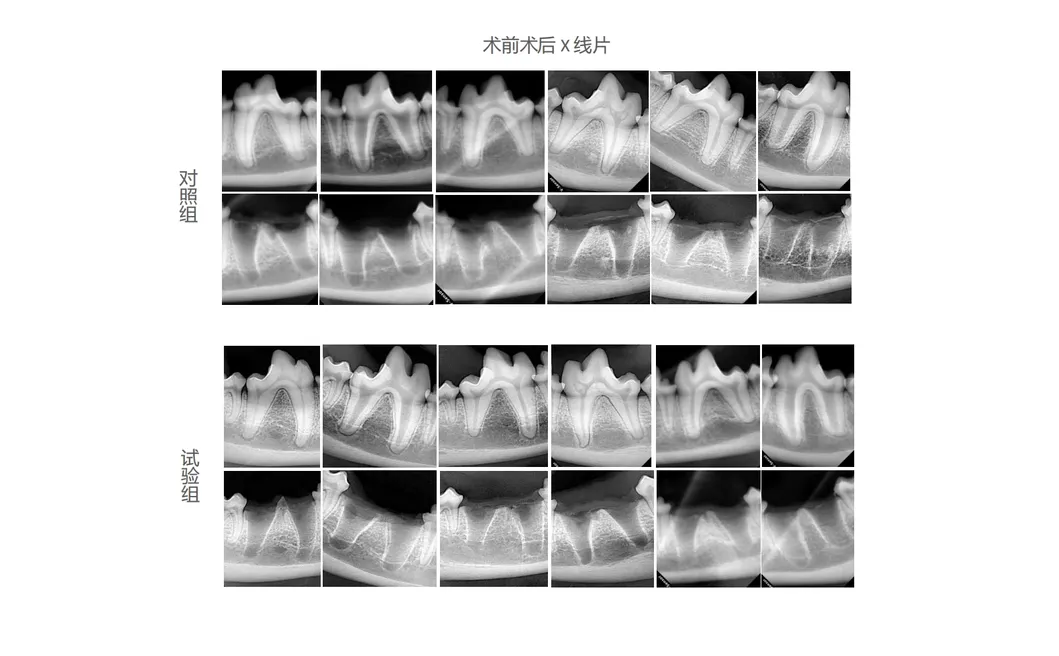

In this study, professional dental tools were tested to analyze the effectiveness of the advanced Golden Cudgel-Pneumatic Dental Elevator Kit. Researchers documented critical factors including physiological parameters, extraction duration, and socket integrity. The study focused on assessing postoperative soft tissue healing and histological evaluations, providing data-driven insights into superior dental performance.